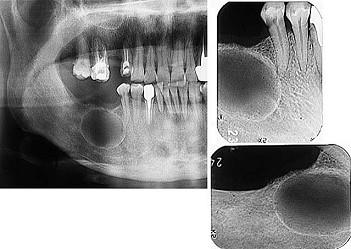

发现下前牙变色,唇侧牙龈一肿物一月余,经X 线检查,结果如图。最可能的诊断是 ( )

A根尖囊肿

B成釉细胞瘤

C牙龈瘤

D根尖脓肿

E牙骨质瘤